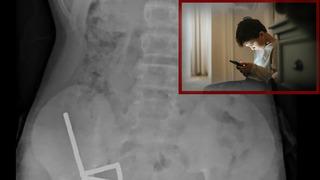

4 gün şiddetli karnı ağrıdı: Gerçek röntgende ortaya çıktı! 100 güçlü mıknatısı görenler hayrete düştü! Tıp tarihine geçti...

Yeni Zelanda’da 13 yaşındaki bir çocuğun çevrim içi alışveriş platformundan satın aldığı yaklaşık 100 yüksek güçlü mıknatısı yutması, tıp dünyasını şoke etti. Tauranga Hastanesi’nde çekilen röntgenlerde ortaya çıkan görüntüler, mıknatısların çocuğun bağırsaklarında ciddi hasara yol açtığını gösterdi. Olay alışveriş platformlarının çocuklar için taşıdığı tehlikeleri bir kez daha gözler önüne serdi. Detaylar haberimizde…